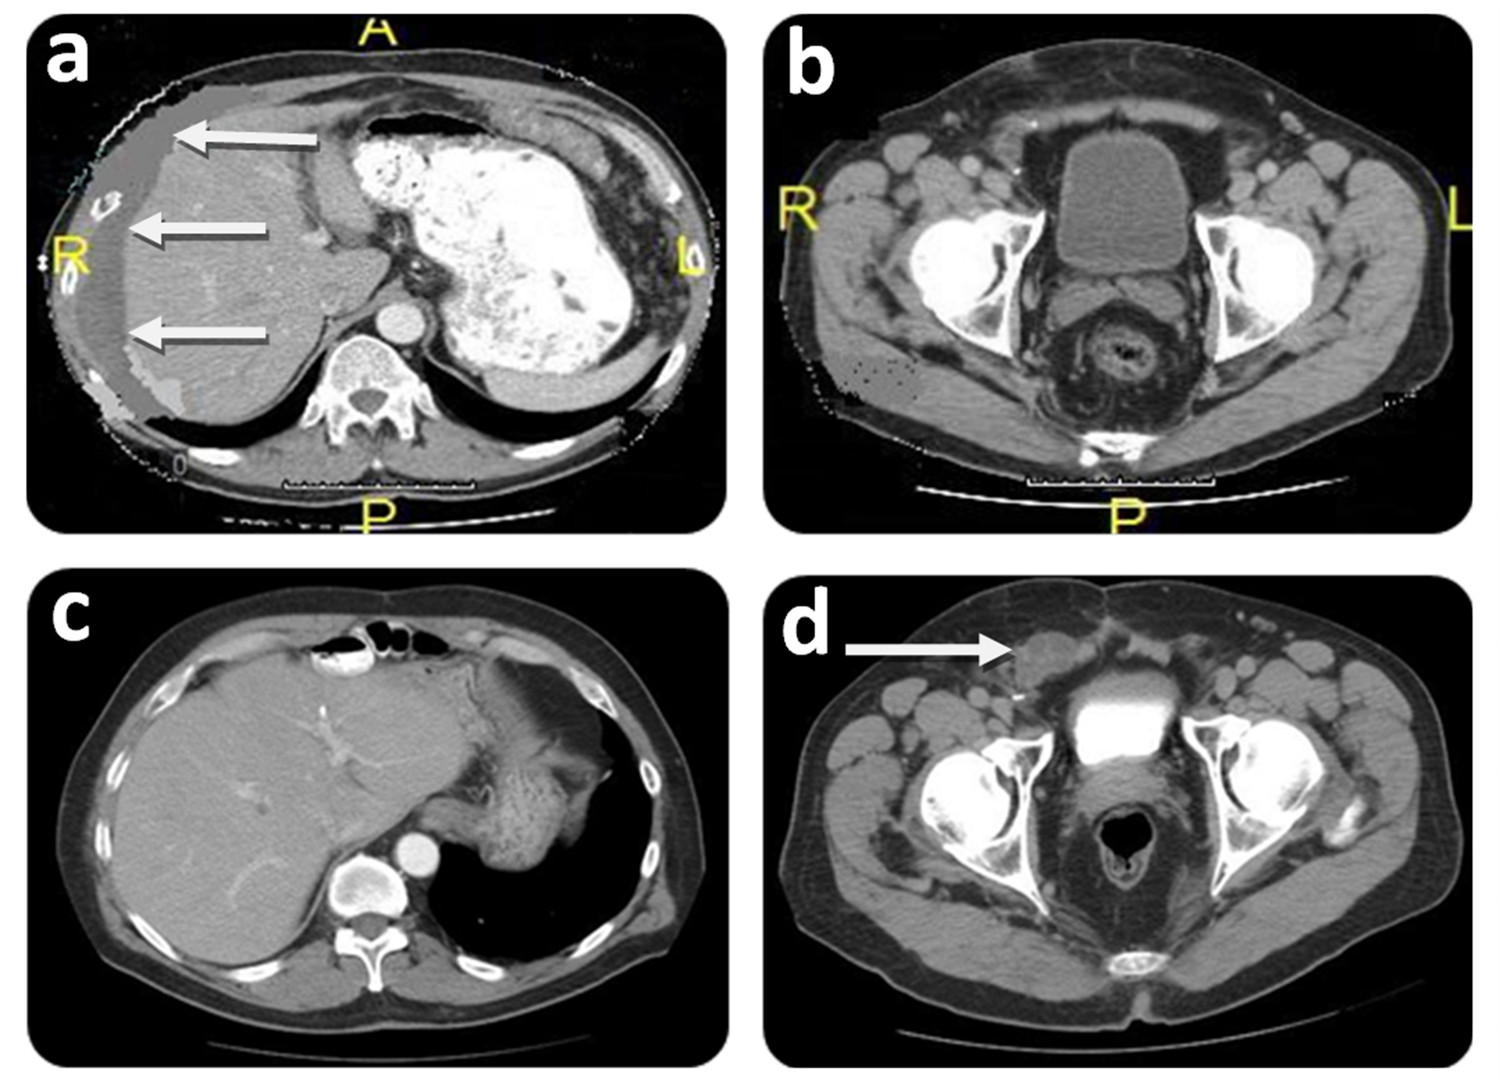

Figure 2.

Initial and follow-up CT scan findings of Case # 1. Preoperative: A) CT scan shows intraperitoneal mucin around liver (white arrows) at initial CRS/HIPEC. A: Anterior; P: Posterior; R: Right side; L: Left side. B) CT scan shows no groin involvement at initial CRS/HIPEC. P: Posterior; R: Right side; L: Left side. Postoperative (36 months after CRS/HIPEC): C) CT scan shows no evidence of disease within the peritoneal cavity at time of groin recurrence. D) CT scan showing groin mass recurrence extending into the scrotum (white arrow).

A 65-year-old male presented with an inguinal and incarcerated umbilical hernia. At the time of surgery, he had mucinous collection in the umbilical hernia sac. The procedure was converted to a laparotomy with an appendectomy and peritoneal biopsy. He required umbilical and inguinal herniorrhaphy, requiring mesh for the latter after excision of the hernia sac. Pathology revealed that the tissue specimen was consistent with mucinous cystadenoma of the appendix with pseudomyxoma peritonei - DPAM. A CT scan revealed multiple areas of mucinous collection around the liver and omental involvement of the tumor (Fig. 2A).

Two months later, the patient was referred to our center specializing on peritoneal surface malignancy. Following a detailed history, the groin was carefully examined and hernia recurrence was ruled out. The CT scan showed diffuse peritoneal implants. No tumor was seen in the groin (Fig. 2B). The patient underwent a CRS/HIPEC (closed technique) using 40 mg of Mitomycin-C for 90 min (30 mg given at time 0 and 10 mg 30 min later) with an inflow temperature maintained at 43° C and an outflow temperature of 41-42° C. The pre/post surgical peritoneal carcinomatosis index (PCI) was 32/0, and complete cytoreduction (CC-0) was achieved. On post operative day 7, the patient developed pneumonia successfully treated with antibiotics and was discharged on post operative day 21 without further complications. He underwent close follow-up, and 36 months after CRS/HIPEC, patient complained of right scrotal edema and a right groin discomfort. No evidence of intra-abdominal disease was evident on CT scan (Fig. 2C); however, and a right groin mass was identified (Fig. 2D). Mucin was obtained with a fine needle aspiration of the scrotum. At the diagnostic laparoscopy, a groin recurrence with extension to the scrotum was strongly suspected and intra-abdominal recurrence was ruled out. Two months later the patient was subjected to exploration of the right groin with radical tumoral resection, resection of abdominal wall, orchiectomy and HCS (Fig. 1). Complete cytoreduction was achieved. The patient was discharged on post operative day 5 without complication. On close follow-up, the patient is alive and without evidence of disease (NED) 88 months from the first CRS/HIPEC, and 50 months from CRS/HCS.